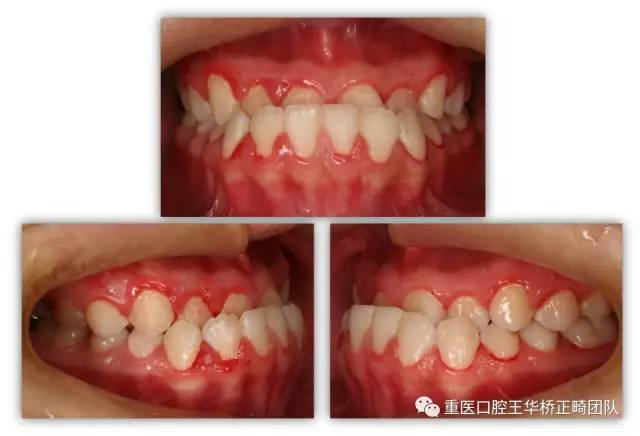

矫正前

口内咬合状况

对于这个严重的成人“地包天”案例我们采用自锁托槽进行单纯正畸掩饰性矫正。

(自锁托槽优点为:舒适、矫治力量柔和、口腔卫生易于维护、牙齿移动快速等)